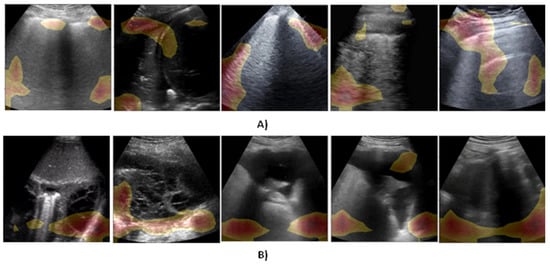

5.4. Explainability Analysis

To understand and interpret the screening decision obtained from the proposed model, the class-related saliency maps for some COVID-19 and pneumonia cases are presented in Figure 3A,B, correspondingly.

Figure 3.

Illustration of visual explanation maps generated by Grad-CAM++ for some of the samples of lung ultrasound frame images after visualization. (A) COVID-19-infected lung, (B) Pneumonia-infected lung.

It could be seen that the GRAD-CAM++ shades the significant lung areas in the ultrasound frame, contributing to making the prediction of the output classes. It is also observable that the model activates diverse zones in the input frame corresponding to different biomarkers to be learned and considered during the screening. These diverse zones adopted for screening are learned intrinsically in the model. Moreover, it is notable that the regions of activations vary from one frame to another, even though they both belong to the same class of infection, hence, these activations can be further enhanced by using more ultrasound data from the same class. For the pneumonia frame, one may observe the presence of pleural consolidations, which is a common biomarker for that disease [33,34]. On the other hand, COVID-19 was demonstrated to show abnormal pleural lines together with upright artifacts in lung ultrasound frames/videos. Figure 3A highlights the location of the lung infection lesions where it is obvious that our model is considering the area in close proximity to the pleural lines for screening the COVID-19 class. This assessment also establishes that the proposed solution could promptly identify the cases suffering from considerable lung abnormalities displayed as B-lines, which enables improved screening of COVID-19 patients.